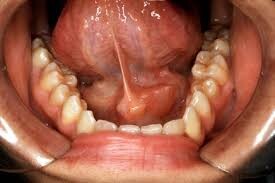

An Abscess – An extremely sensitive, painful bump on your gums that looks like a pimple is likely an abscess. An abscess is due to a bacterial infection and occurs as pus collects under the gum, forming a bump or boil.

There are different types of abscesses, including a periodontal abscess, which is usually caused by periodontitis (advanced gum disease), and a periapical abscess, which is an infection at the tip of your tooth’s root from tooth decay or an injury. A periapical abscess usually presents as a bump on the gums above or below the affected tooth.

If you do have an abscess, it will often be accompanied by other symptoms including:

Swollen gums

Bad breath

Sensitivity to hot and cold

Fever

Discharge

Fatigue

Facial swelling

Persistent pain that may spread to the ear, jaw and neck

It’s important to have an abscess evaluated and treated. It won’t go away on its own. While it can drain and provide temporary relief, the infection will still be present and can spread to the jaw and supporting tissues. In rare cases, a dental infection can reach the brain and cause serious health complications.

Treatment for an abscess will involve treating the infection, whether through periodontal care or a root canal, and, sometimes, antibiotics. We might also drain the abscess to give you immediate relief.